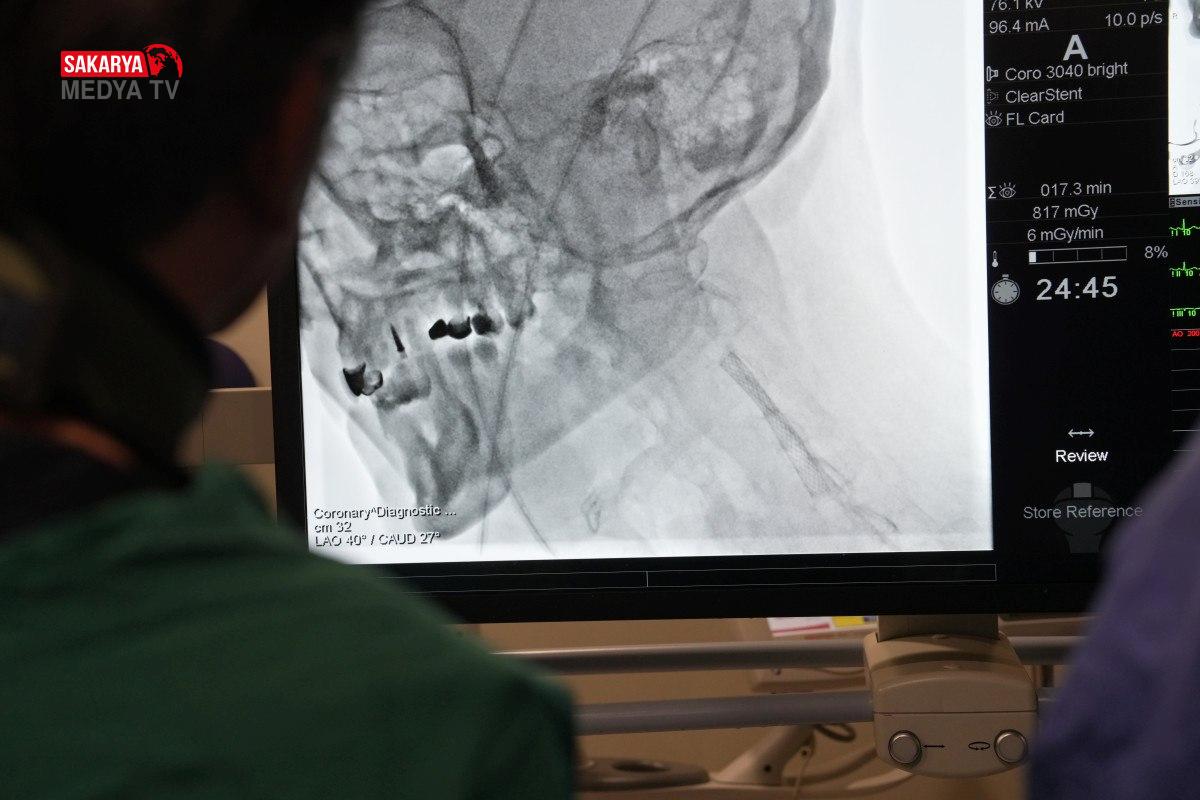

Haber Merkezi Türkiye son 20 yılda sağlık alanında büyük mesafe katetti. Dünyada yaşanan sağlık krizlerinde Türkiye’nin sağlık gücü de kanıtlandı. Bu gelişme sadece devlet hastanelerinde olmadı. Özel hastaneler de uluslararası arenada ciddi konumlar elde etti. Medipol Acıbadem Bölge Hastanesi’nde, Kardiyoloji Uzmanı Prof. Dr. Ertuğrul Okuyan’ın öncülüğünde; özellikle Mısır, Pakistan, Tunus ve Cezayir’den gelen doktorlara “İleri Stent Teknikleri” ve “Kronik Damar Açma” gibi devrim niteliğindeki teknikler hakkında uygulamalı eğitimler verildi. Eğitimler sırasında teorik bilgilerin yanı sıra, canlı operasyonlarla betonlaşmış damarlar yeniden hayata döndürüldü.

Teknolojinin gelişmesi ve hekimlerimizin denetimleriyle birlikte, eskiden açık cerrahiyle yapılan işlemleri artık kapalı yöntemlerle yapabildiklerini ifade eden Prof. Dr. Okuyan, “Kireçli ya da tıkalı damarlarda stent ve balon işlemlerini uyguluyoruz. Başarılı sonuçlar da alıyoruz. Ayrıca damar içi taş kırma işlemleri de yapıyoruz.

Bu yöntemler, zor hastaları tedavi etmemize olanak sağlıyor. Yurt dışından gelen çok değerli meslektaşlarımıza bu konularda teorik ve pratik eğitimler veriyoruz. Bilgi ve donanımımızı meslektaşlarımıza aktarma imkânı buluyoruz.” şeklinde konuştu.

Yapılan açıklamanın ardından canlı cerrahi operasyonlara geçildi. Prof. Dr. Okuyan,Pakistan, Tunus, Cezair ve Mısır’dan gelen doktorlara cerrahi işlemleri adım adım anlatma imkânı buldu.